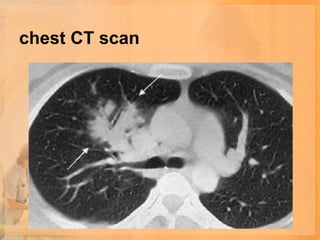

chest CT scan

• Chest CT scan